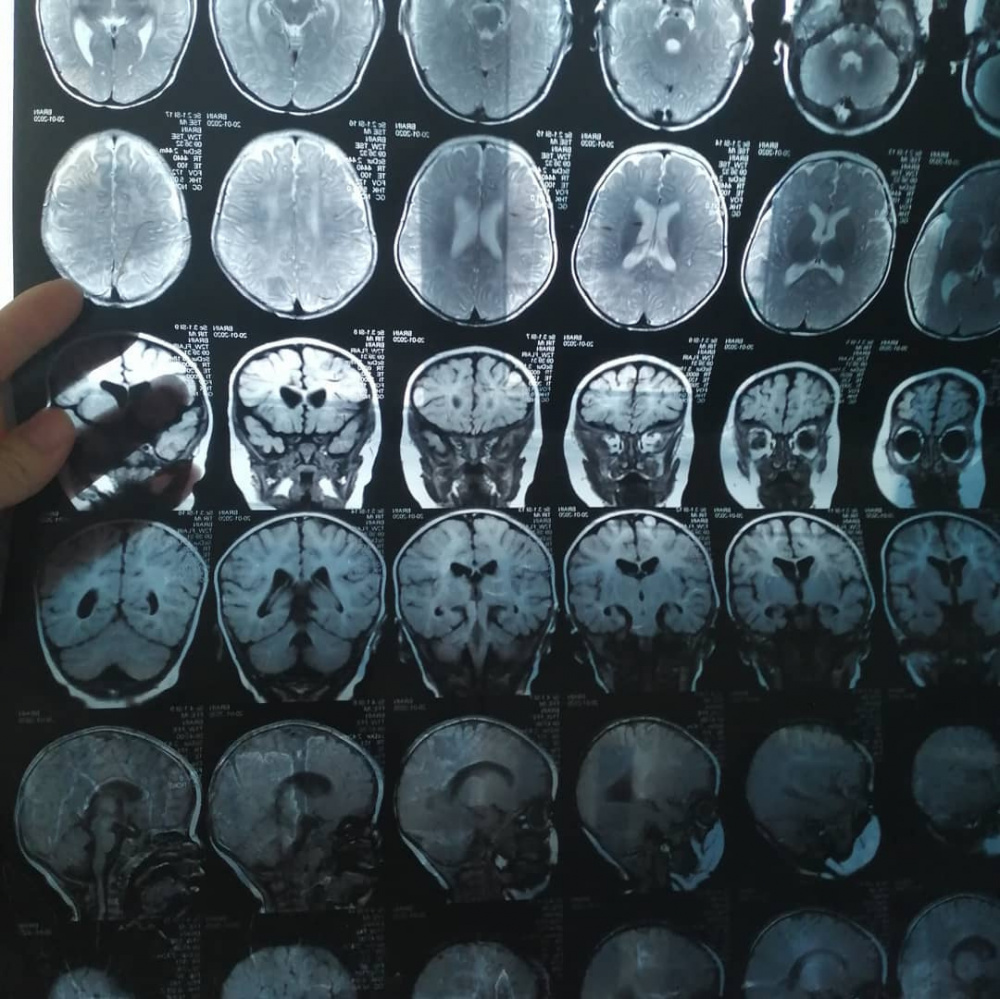

Бегимай Токтосунова - мать-одиночка. После развода на ее попечении остались дочь с тяжелой формой ДЦП и больная мама. Почти шесть лет Бегимай тянет на себе все, но заработанного хватает только на бытовые нужды и поддерживающие препараты для ее дочери и мамы. У девочки, помимо детского церебрального паралича, сходящееся косоглазие с двух сторон и двусторонняя деформация голеностопного сустава, а также ряд сопутствующих заболеваний.

Айкол уже перенесла две операции в Бишкеке по исправлению двусторонней деформации голеностопного сустава. Только желаемых результатов операции не дали.

"Узнала, что за границей можно провести более сложную, но и более эффективную операцию. Начала собирать информацию. Обратилась к врачам в Турции. Они дали гарантию, что в нашем случае ее косолапость можно исправить. Операция будет стоить $25 тыс. Но проблема в том, что у меня нет таких денег, и я даже не знаю, как столько заработать за короткий срок", - говорит Бегимай.